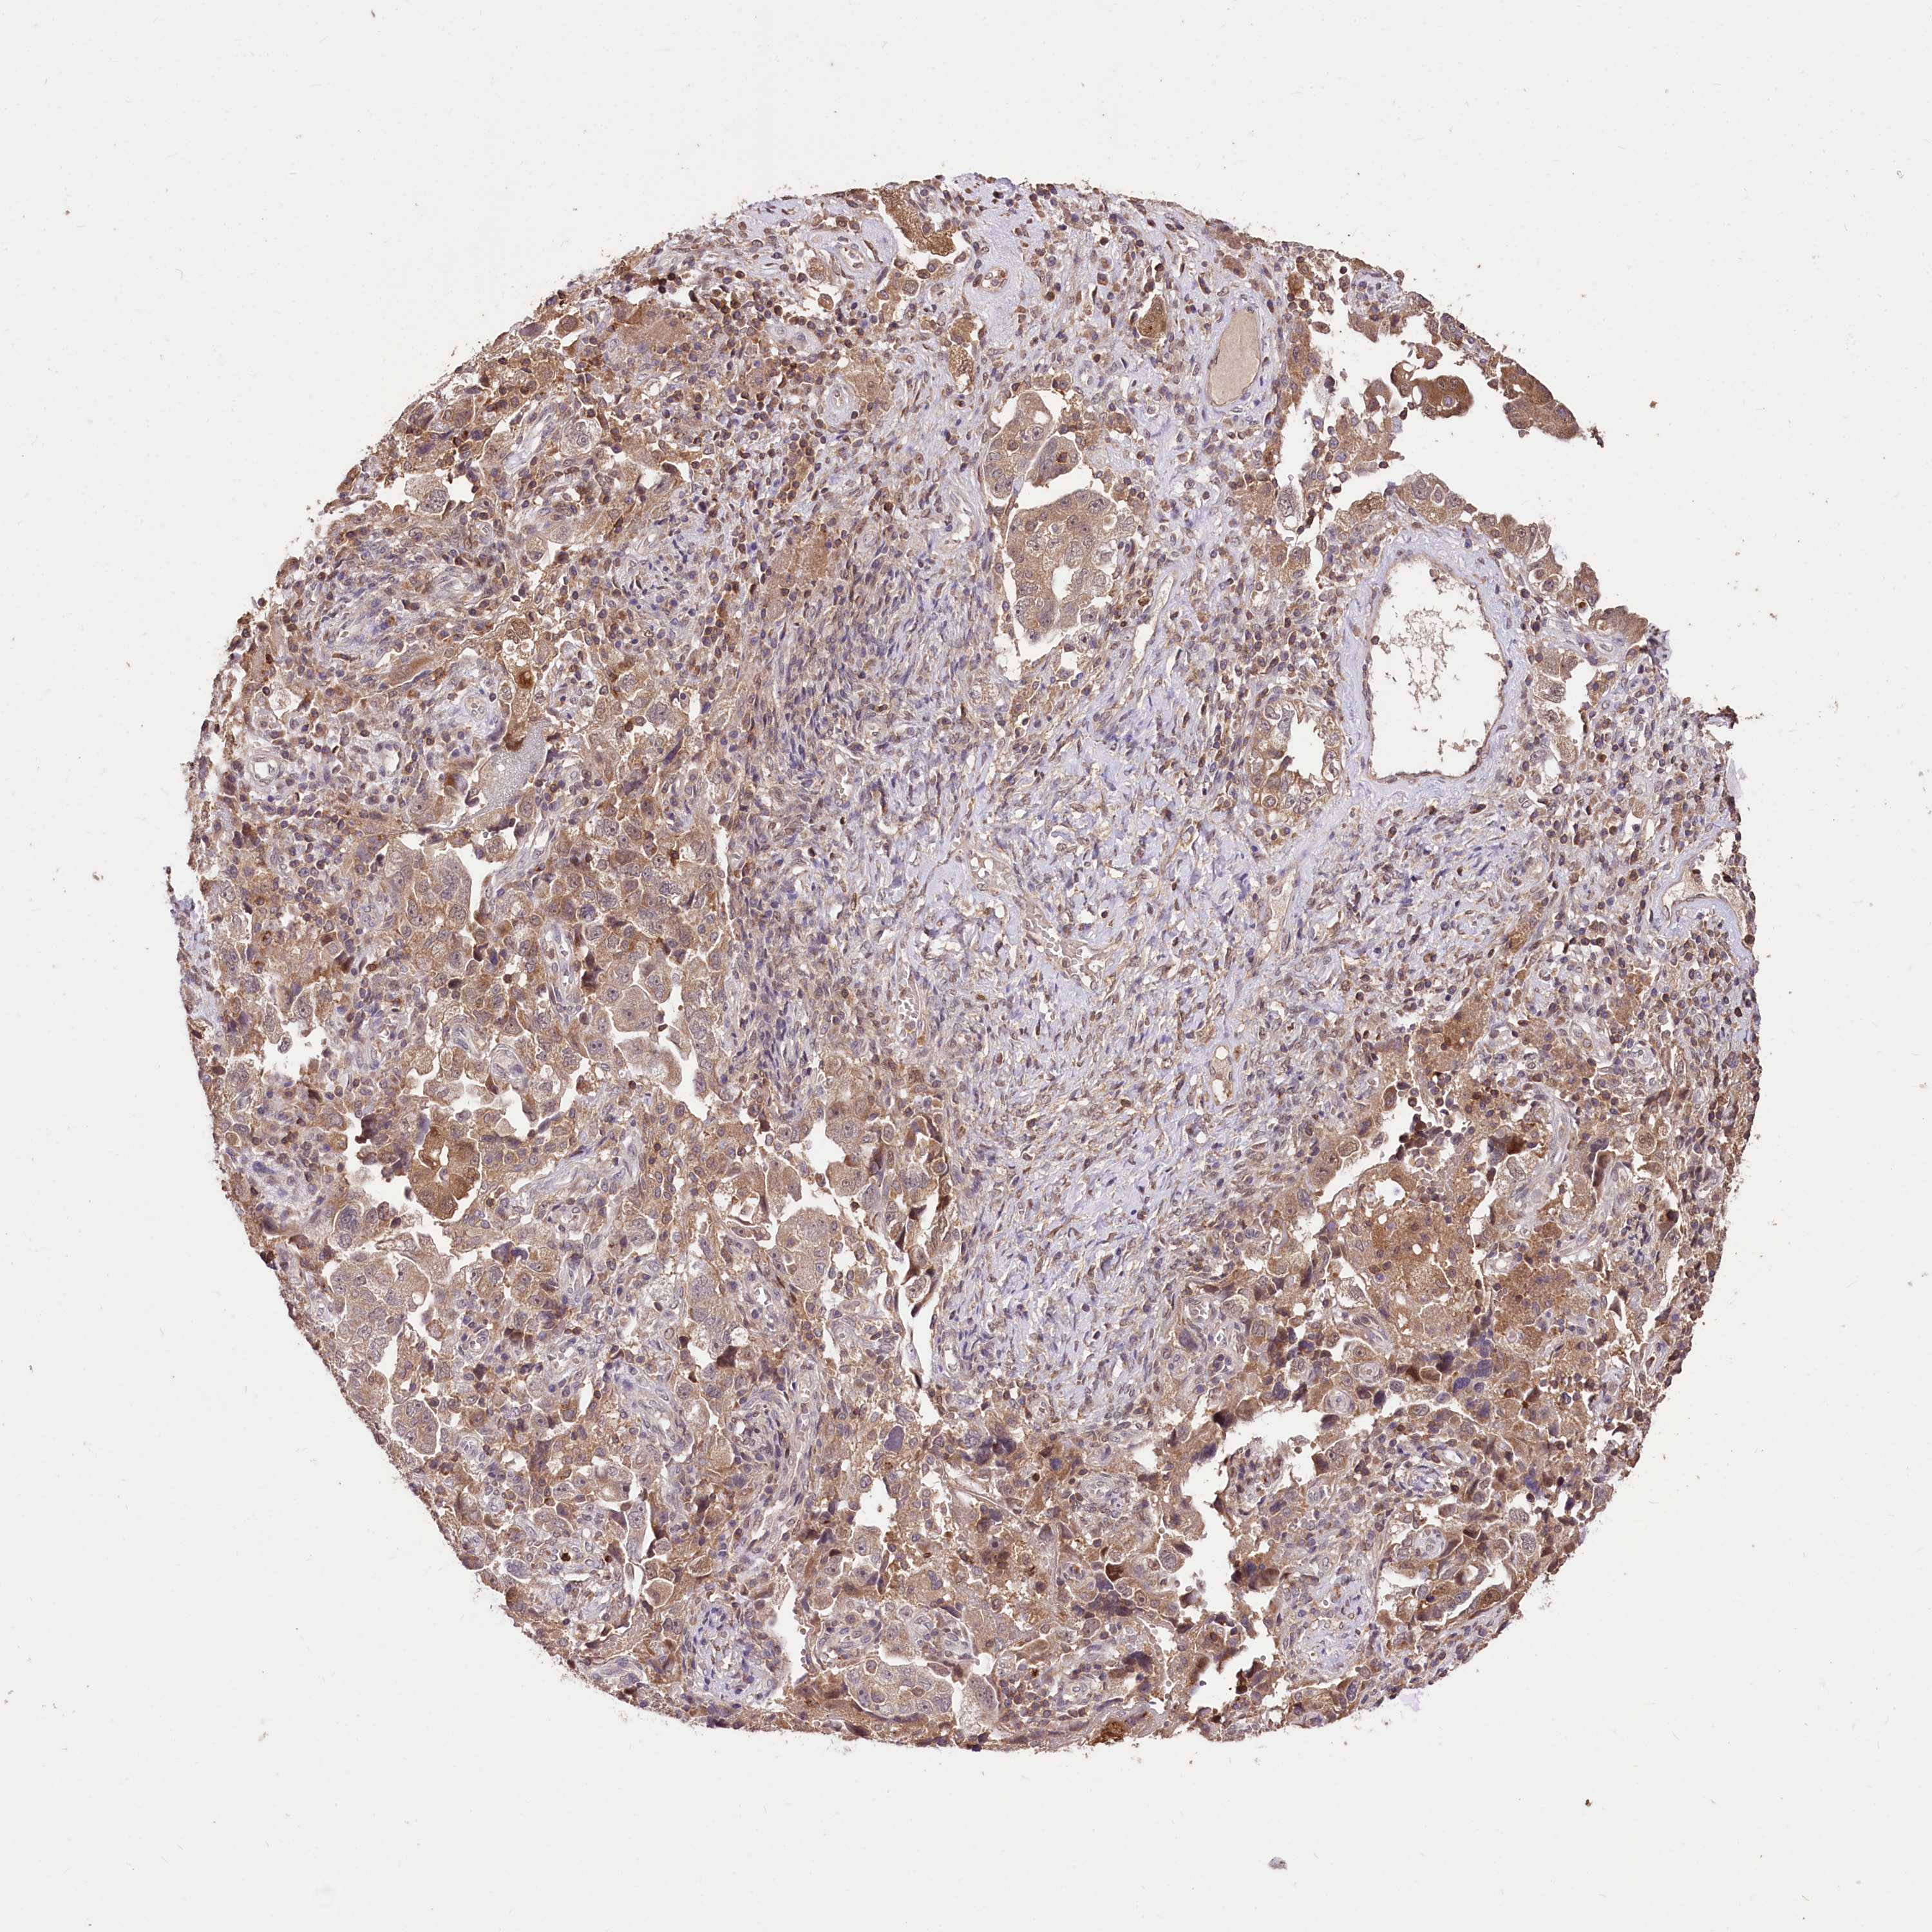

OVARIAN CANCER - Protein expressioni

A mouse-over function shows sample information and annotation data. Click on an image to view it in a full screen mode. Samples can be filtered based on level of antibody staining by selecting one or several of the following categories: high, medium, low and not detected. The assay and annotation is described here.

Note that samples used for immunohistochemistry by the Human Protein Atlas do not correspond to samples in the TCGA dataset.

Antibody stainingi

Antibody staining in the annotated cell types in the current human tissue is reported as not detected, low, medium, or high, based on conventional immunohistochemistry profiling in selected tissues. This score is based on the combination of the staining intensity and fraction of stained cells.

Each image is clickable and will lead to virtual microscopy that enables deeper exploration of all samples and also displays staining intensity scores, fraction scores and subcellular localization as well as patient and tissue information for each sample.

Antibody HPA037811

Antibody HPA037812

Staining

High

Medium

Low

Not detected

Intensity

Strong

Moderate

Weak

Negative

Quantity

>75%

75%-25%

<25%

None

Location

Nuclear

Cytoplasmic/membranous

Cytoplasmic/membranous,nuclear

Cystadenocarcinoma, serous, NOS